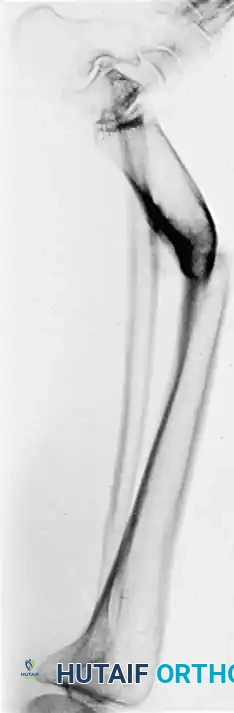

Fig. 6: (A, B) Varus malunion of the distal tibia. (C) Osteotomy of the tibia and fibula with reduction maintained by a circular external fixator. (D, E) Tibial union obtained with normal alignment.